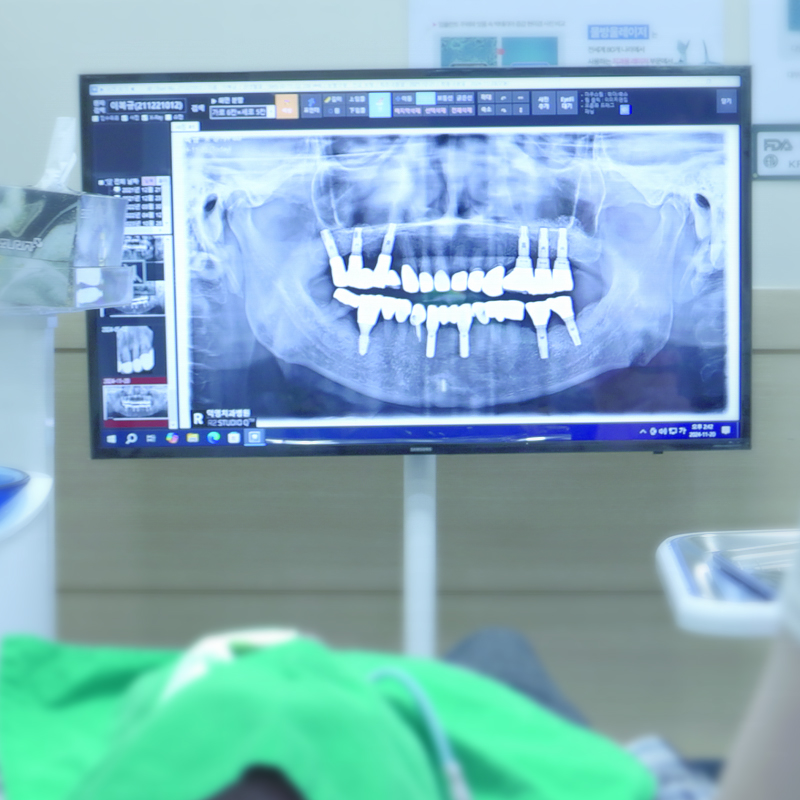

임플란트는 시술 후 관리가 더 중요합니다

임플란트 식립 이후에 제대로 된 유지 관리가 이뤄지지 않는다면, 여러 문제가 발생할 수 있습니다.

치태나 치석이 쌓여 치주염과 유사한 증상인 잇몸이 붓고 출혈이 발생하는 임플란트 주위염이 발생할 수 있습니다.

임플란트 주위염이란?

초기에는 가벼운 잇몸 염증으로 시작되지만, 진행되면 뼈 손실까지 초래하여 임플란트를 유지하기 어렵게 만들 수 있습니다.